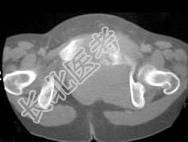

- 单项选择题女,54岁, 因反复左髋、左下肢痛伴左下肢活动障碍约半年,结合所提供的图像, 最可能的诊断是 ( )

A、骨髓瘤

B、滑膜肉瘤

C、骨转移瘤

D、尤文肉瘤

E、骨巨细胞瘤